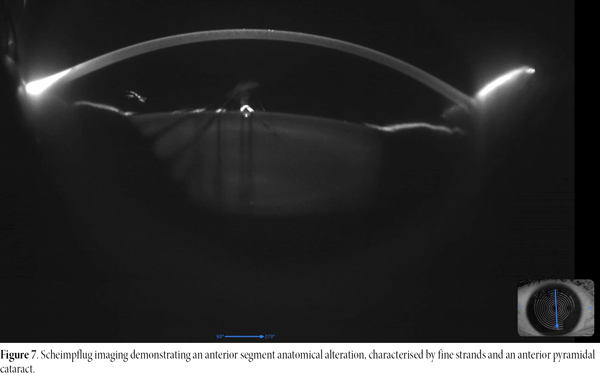

Preoperatively, her uncorrected visual acuity was LogMAR 1.33. Refraction testing revealed a best-corrected visual acuity of LogMAR 0.10, with a refractive error of -5.75 D sphere and -1.00 D cylinder at 12°. Preoperative assessments —including ocular response analysis (Fig. 4), dry eye evaluation (Fig. 5), corneal topography and pachymetry (Fig. 6)— were within normal limits. Scheimpflug imaging demonstrated an anterior segment anatomical alteration characterised by the strands and the pyramidal cataract (Fig. 7). Optical coherence tomography revealed a normal optic disc, while macular imaging showed a parafoveal pucker without oedema (Fig. 8).

Figure 7. Scheimpflug imaging demonstrating an anterior segment anatomical alteration, characterised by fine strands and an anterior pyramidal cataract.